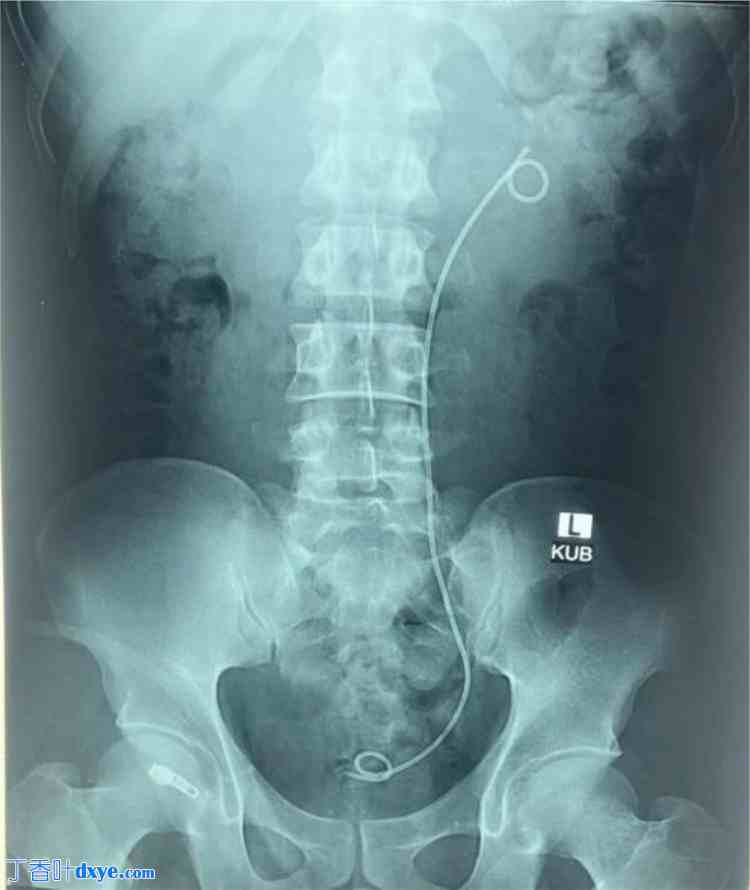

由于上述肾功能检查结果异常,且肌酐清除率低于 30 毫米/分钟,因此未进行造影检查。在对症治疗和广谱抗生素治疗后,在局部麻醉下,通过超声引导下经皮右肾造瘘术 (PCN) 抽吸尿管瘤。术后优化后,右侧输尿管气压弹道碎石术,置入双J管6French支架缓解梗阻(图4)。

图4.

术后X光KUB显示右侧PCN管和DJ支架置入,左肾内有较大结石。